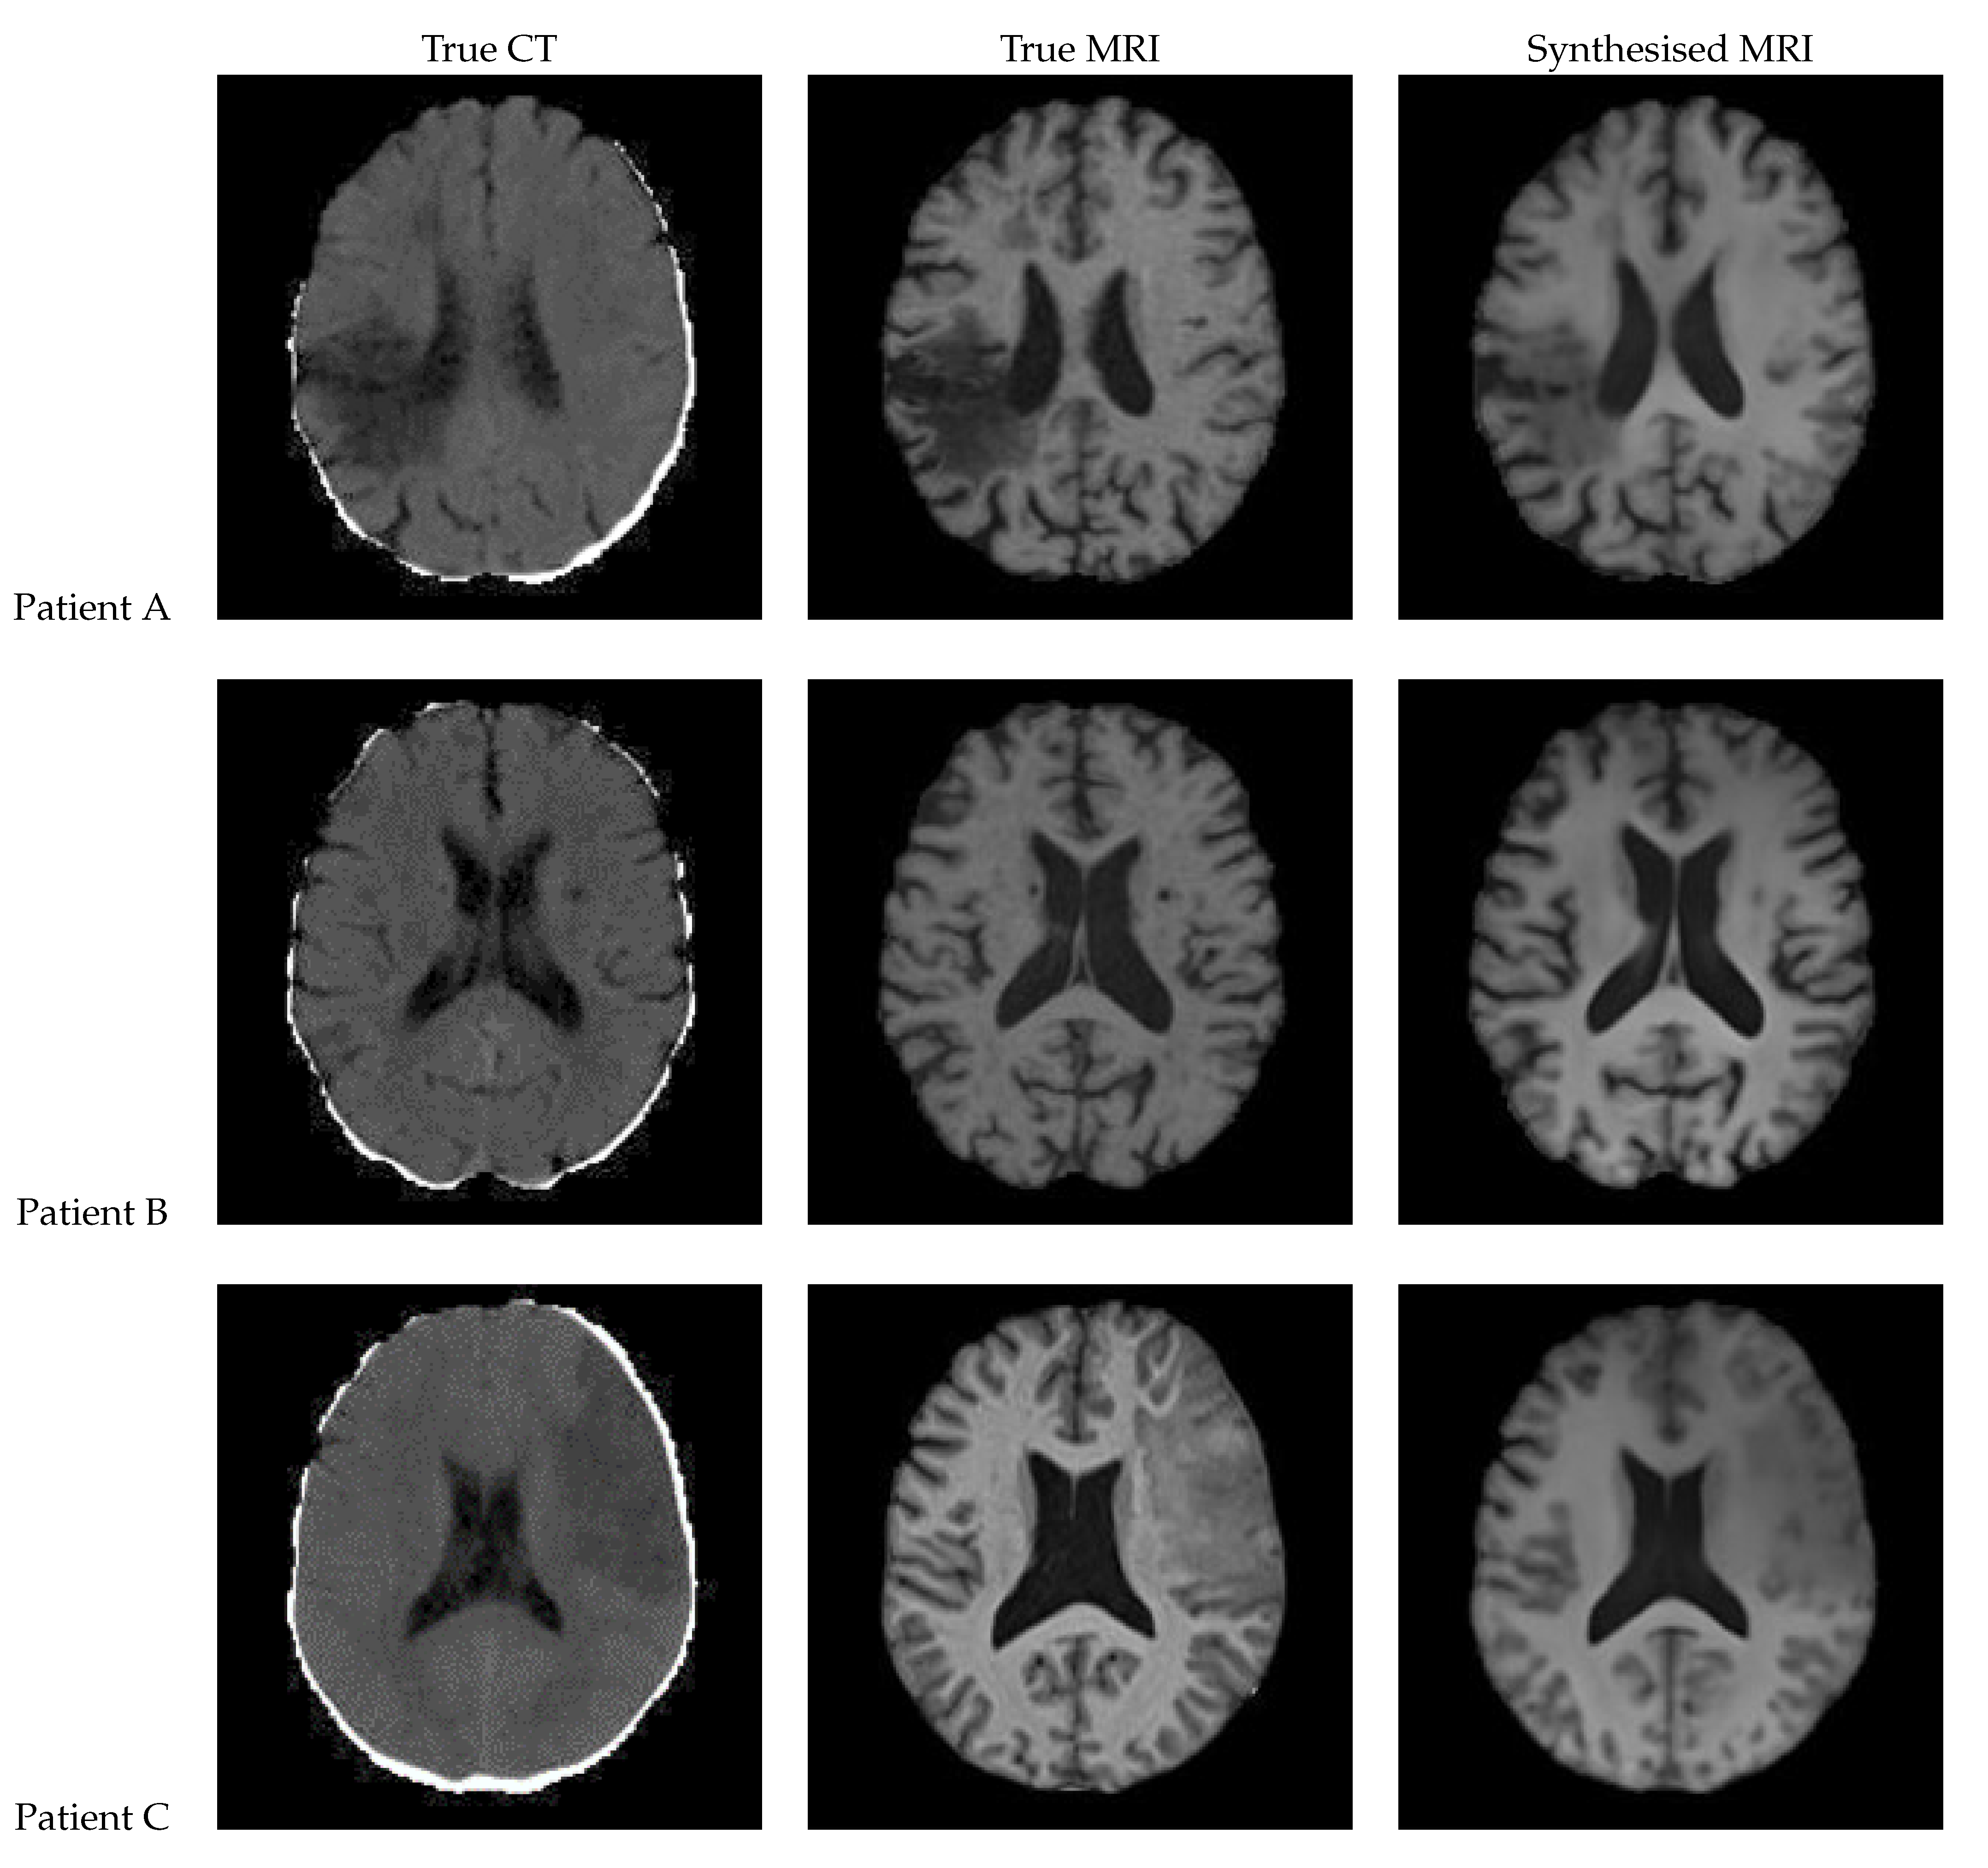

Figure 12 shows a sample slice of the synthetic MRI generated by a 3D UNet for three patients in the test set, along with the corresponding true MRI and CT slices. Patient A presents a large lesion, which can also be seen in the synthesised MRI, but with reduced contrast and less precise borders. Patient B shows a similar overall contrast to the true MRI. Patient C displays a very large, faint lesion that is not clearly visible in the synthetic MRI.

Figure 12. Axial slices of CT Scans (Left), True MRIs (Centre), and Synthetic MRIs generated by UNet (Right).

True CT True MRI Synthesised MRI

Patient A

Patient B

Patient C